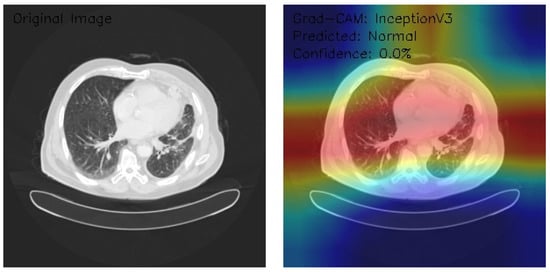

Analysis of InceptionV3 Model Performance on Lung CT Images with Grad-CAM Visualization

The results section of this study presents the detailed findings from an advanced analysis of three axial chest CT images processed using the InceptionV3 deep learning model. This analysis leverages the sophisticated capabilities of Grad-CAM to provide a comprehensive visualization of the regions within the CT images that the model identifies as significant for its predictions. Combining the robust classification performance of the InceptionV3 architecture with the interpretability offered by Grad-CAM, this approach not only evaluates the model’s predictive accuracy but also elucidates the spatial patterns of attention within the medical imaging context. This dual focus allows for a deeper understanding of the diagnostic potential of deep learning in radiology and the interpretive transparency essential for clinical application. The following results detail these observations, highlighting key insights into the model’s behavior and implications for automated diagnostic processes.

Figure 9 shows that the CT image reveals clear lung fields with well-defined bronchial structures, indicating no abnormalities in the original scan. The Grad-CAM visualization highlights a distinctive rainbow-like activation pattern, predominantly focusing on the central and bilateral lung fields with symmetric intensity. Despite these detailed attention patterns, the model classifies the image as Normal with a confidence score of 0.0%, pointing to significant issues in confidence calibration. This suggests the model can identify relevant anatomical regions but lacks reliability in translating these insights into confident and actionable classifications. Further calibration and optimization are necessary for clinical applicability.

Figure 9.

Grad-CAM visualization using InceptionV3 for lung CT scan with normal prediction. (Source: author’s analysis from data, 2024).

Figure 10 shows that the CT image analysis highlights scattered nodular opacities, suggesting potential abnormalities. The Grad-CAM visualization indicates peripheral activation patterns, with a notable focus on lateral lung regions. The heatmap’s color gradients suggest varying feature importance across these areas. Despite identifying relevant features, the model classifies the image as Malignant with a confidence score of 0.0%, reflecting significant uncertainty. This indicates a disconnect between the model’s feature detection and its confidence in classification, emphasizing the need for recalibration and potential retraining to enhance diagnostic reliability and decision-making accuracy.

Figure 10.

Grad-CAM visualization with InceptionV3 for lung CT image analysis reveals scattered nodular opacities, indicating possible abnormalities. (Source: author’s analysis from data, 2024).

Figure 11 shows that the CT image displays interstitial patterns, indicative of potential structural abnormalities. The Grad-CAM visualization highlights strong activation centrally and in the right lung, with an asymmetric attention distribution favoring the right hemithorax. Despite this focused feature analysis, the model classifies the image as Normal with a confidence score of 0.0%, suggesting significant limitations in the model’s confidence calibration and decision-making reliability. The mismatch between observed features and classification confidence underscores the need for model refinement, particularly in aligning activation insights with robust, actionable predictions.

Figure 11.

Grad-CAM visualization using InceptionV3 for lung CT scan with malignant prediction. (Source: author’s analysis from data, 2024).

This analysis evaluates three axial chest CT images processed by an InceptionV3 model with Grad-CAM visualizations, focusing on attention regions and classification outcomes. Image 1 shows clear lung fields with symmetric central activation, classified as Normal with 0.0% confidence. Image 2, with scattered nodular opacities, displays peripheral activation patterns and is classified as Malignant, again with 0.0% confidence. Image 3 exhibits interstitial patterns with strong central and right-sided activation, also classified as Normal with 0.0% confidence. The Grad-CAM visualizations highlight relevant anatomical features, but the model’s uniform low confidence scores reveal calibration and classification inefficiencies. Recommendations include the recalibration of confidence scoring, fine-tuning classification layers, and integrating ensemble methods. While feature detection appears robust, these refinements are critical for clinical reliability and decision-making.